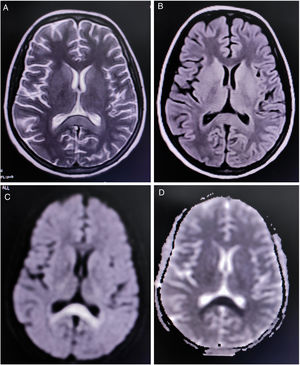

Complete blood cell count revealed mild anemia (hemoglobin 9.0g/dL), elevated erythrocyte sedimentation rate (80mm/h), relative lymphopenia, and thrombocytopenia (platelets count=60,000/μl (reference range 150,000–450,000). Liver function tests showed an approximately two-fold rise of the transaminases. Renal and thyroid function tests and blood glucose levels were within normal limits. Diagnostic tests were negative for endemic infections like malaria, dengue, Leptospira, Japanese encephalitis, and scrub typhus. However, Typhi Dot IgM (ELISA) was found to be positive. Magnetic resonance imaging (MRI) of the brain demonstrated a non-enhancing hypertense lesion on T2-weighted image and T2-FLAIR, with substantial diffusion restriction on diffusion-weighted imaging sequences, involving the splenium of the corpus callosum, suggestive of boomerang sign (Fig. 1). MR angiography of the brain was normal. Cerebrospinal fluid (CSF) studies revealed lymphocytic pleocytosis (10cells/μl, all lymphocytes), slightly low glucose levels (48mg/dL, normal range 50–80mg/dL), and normal protein levels (46mg/dL, normal range 15–50mg/dL) without any albuminocytologic dissociation. Oligoclonal bands, anti-aquaporin 4, and anti-myelin oligodendrocyte glycoprotein antibodies were not detected in the CSF and serum. However, serum GQ-1b-IgG antibodies were positive. CSF polymerase chain reaction for relevant neuroviruses and tuberculosis and tests for neurosarcoidosis and neuroborreliosis were negative. Tests for Mycoplasma, Campylobacter jejuni, influenza, HIV, and hepatitis viruses were also non-reactive. Sensory and motor nerve conduction studies revealed bilateral sensory-motor polyneuropathy, predominantly axonal; needle electromyography and repetitive nerve stimulation tests were unremarkable. Blood cultures resulted positive for Salmonella typhi.

Neuroimaging in this patient showed an uncommon radiological finding, i.e. cytotoxic lesion of the corpus callosum (CLOCCs), popularly known as the “boomerang sign”.8 CLOCCs, especially involving the splenium, are seen in association with cerebrovascular events, demyelinating disorders, metabolic disorders, seizures, medications, infections, malignancies, trauma, high-altitude cerebral edema, preeclampsia toxicity, posterior reversible encephalopathy syndrome, autoimmune encephalitis, post-partum cerebral angiopathy, and vaccination, among others.9,10